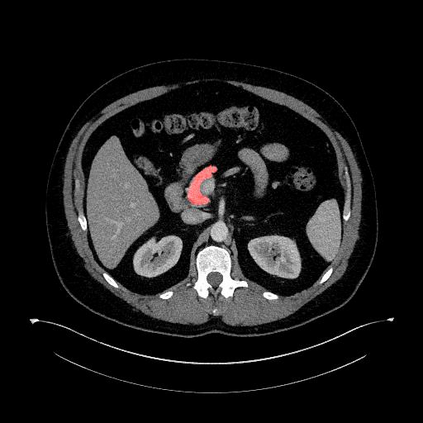

In this paper, we adopt 3D Convolutional Neural Networks to segment volumetric medical images. Although deep neural networks have been proven to be very effective on many 2D vision tasks, it is still challenging to apply them to 3D tasks due to the limited amount of annotated 3D data and limited computational resources. We propose a novel 3D-based coarse-to-fine framework to effectively and efficiently tackle these challenges. The proposed 3D-based framework outperforms the 2D counterpart to a large margin since it can leverage the rich spatial infor- mation along all three axes. We conduct experiments on two datasets which include healthy and pathological pancreases respectively, and achieve the current state-of-the-art in terms of Dice-S{\o}rensen Coefficient (DSC). On the NIH pancreas segmentation dataset, we outperform the previous best by an average of over 2%, and the worst case is improved by 7% to reach almost 70%, which indicates the reliability of our framework in clinical applications.